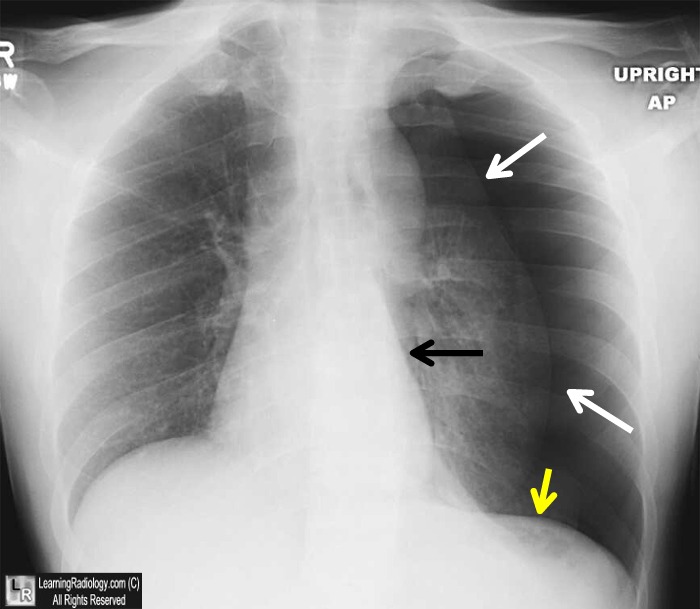

图4 张力性气胸。胸部X线片显示左侧张力性气胸(白箭头),心影右移(黑箭头)和左侧横膈膜凹陷(黄箭头)。